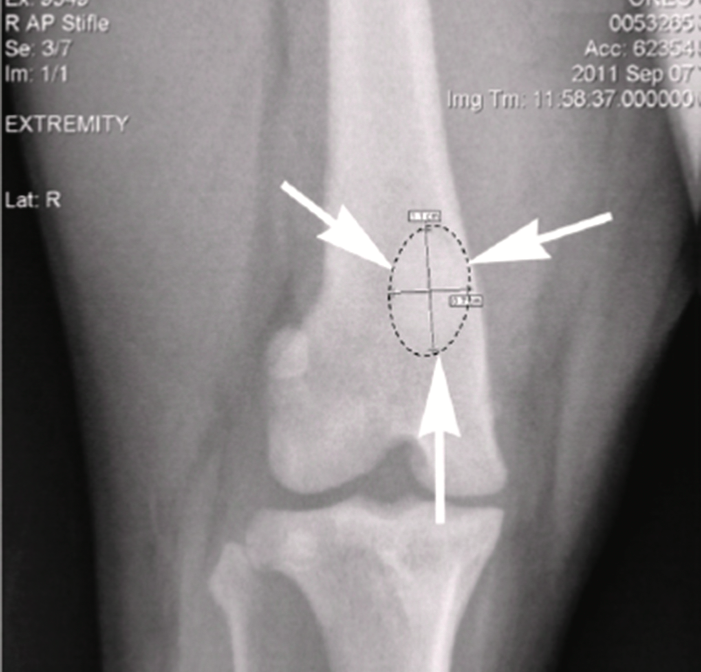

X-ray of original hind stifle joint and patella.

To help Oreo, OIC obtained a donated patella that was used to generate a scaled digitized copy. A biomedical engineer then converted the file into a computer-aided design (CAD) model. X-ray radiographs of Oreo’s other patella were then used to modify the CAD design to match his femur.